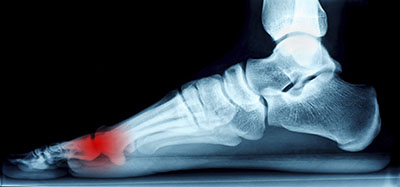

Morton’s neuroma may develop when the tissue around one of the nerves leading to your foot begins to thicken. When this occurs, you may experience some discomfort as if you were standing on a pebble stuck in your shoe. Most symptoms will not appear outwardly and will be experienced in the form of a sharp, burning pain in the ball of the foot, as well as a stinging or burning feeling in the toes that may sometimes lead to numbness.

Some factors that contribute to the formation of Morton’s neuroma include wearing high heels or ill-fitting shoes that put extra pressure on your toes or the balls of your feet. There has also been a tie to the development of Morton’s neuroma and certain high-impact sporting activities. Activities you may want to avoid from participating in too frequently include both jogging and running. Too much repetitive trauma can cause a strain on the feet and increase the chances of developing a foot complication. Other sports that require the use of tightly worn shoes, such as skiing or rock climbing, may also increase your chances of getting Morton’s neuroma. Certain foot deformities can also lead to the development of Morton’s neuroma. Some of these deformities that increase the likelihood of getting this condition include bunions, hammertoes, and flat feet.